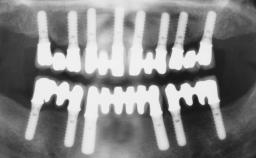

Immediate Loading of Six Implants in the Mandible and Six Implants in the Maxilla and Final Restoration with Full-Arch CAD/CAM Metal Framework FDPs Involving Digital Planning and Guided Surgery

Immediate loading of dental implants is increasingly popular with clinicians and patients. The idea of delivering a restoration directly after implant insertion,combined with a less invasive procedure (flapless protocol), has made treatment protocols involving dental implants more accessible to dentists and patients. However,immediate-loading concepts require sophisticated and exact planning. To facilitate this, conventional panoramic tomographs and periapical radiographs are often taken with the patient wearing a radiographic template simulating the preoperative prosthetic design. However, these radiographs do not provide all the necessary information. In addition, some protocols call for conventional surgical templates fabricated on the diagnostic cast. These will inform the bone drilling points and drill angles, but do not reference the underlying anatomical structures or provide exact 3-D guidance.

# of Implants 12